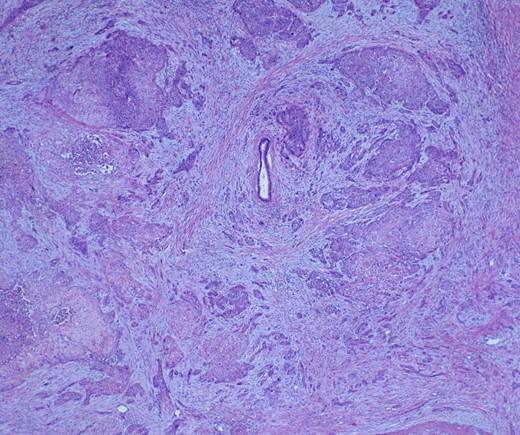

She underwent an open pylorus-preserving pancreatoduodenectomy with segmental superior mesenteric vein resection with primary reconstruction (ISGPS Type 3) without complication. Final pathology demonstrated a 3.6-cm poorly differentiated adenosquamous carcinoma with SMV invasion into the intima (Fig. 2), 1 of 24 regional lymph nodes with metastatic carcinoma, lymphovascular and perineural invasion (Fig. 3), and an 85% squamous differentiation (Fig. 4). There was a partial pathologic response (College of American Pathologist Grade 2) within the primary tumor and involved lymph node tumor [7]. There was noted to be tumor extension within 1 mm of the superior mesenteric artery margin (Fig. 5) (R1 status) with negative additional margins. She recovered without complications and was discharged home on the fourth post-operative day. Repeat staging CT imaging demonstrated no evident disease. She was initiated on adjuvant systemic therapy.

Adenosqumous carcinoma with both components (adeno and squamous) A19 Cytokeratin 7 immunostain, highlighting the adenocarcinoma, and p40 immunostain, highlighting the squamous carcinoma component